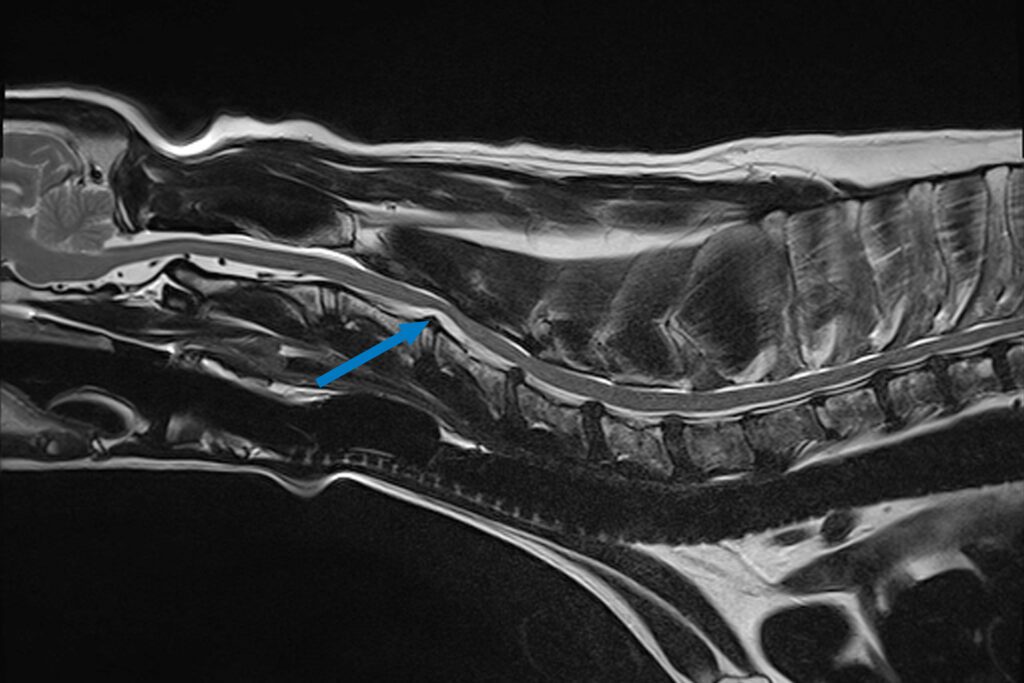

Our 1.5T MRI produces excellent contrast between various soft tissue structures in any plane of the body and is the gold standard for spinal imaging. In this instance, it was needed to visualise all the discs in Bryn’s neck, his spinal cord and nerve roots to identify what exactly was stopping the signals from his brain reaching his legs and where that was located. MRI revealed a hydrated disc extrusion at the level of C3-C4, which was compressing the spinal cord and starting to affect the nerves that control his breathing.